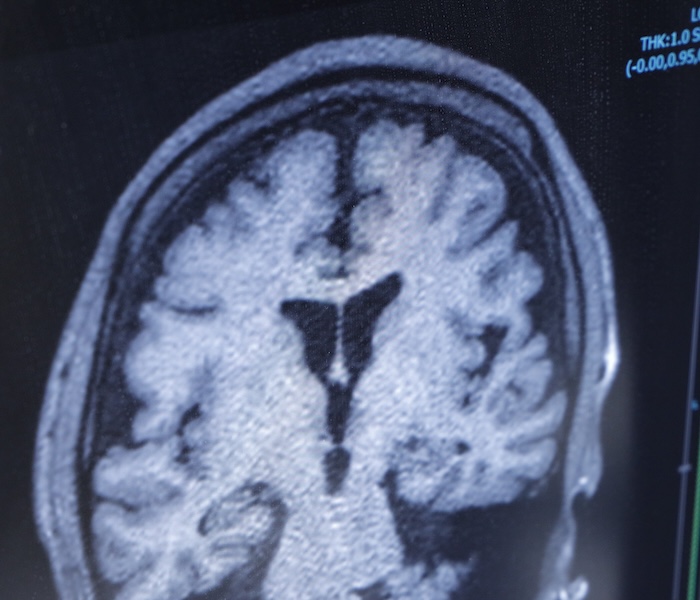

最新の1.5TMRIおよびCTを完備

当院では、MRI、CT画像の精密な読影を行い、脳腫瘍・脳動脈瘤・認知症といったさまざまな脳疾患の 診断・予防・治療まで総合的にサポートします。MRIはAI技術を活用した高画質・短時間撮影が可能で、患者様の負担を軽減しながら、微細な脳構造まで正確に評価します。

また、解析ソフト(VSRAD)を用いた脳の客観的評価により、認知症の早期発見や経過観察、治療方針の立案にも力を入れています。